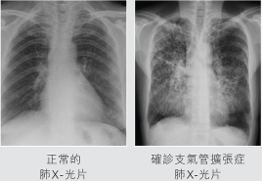

- Imaging: A chest X-ray may show abnormalities, but a CT scan of the lungs is the most accurate method for diagnosis.